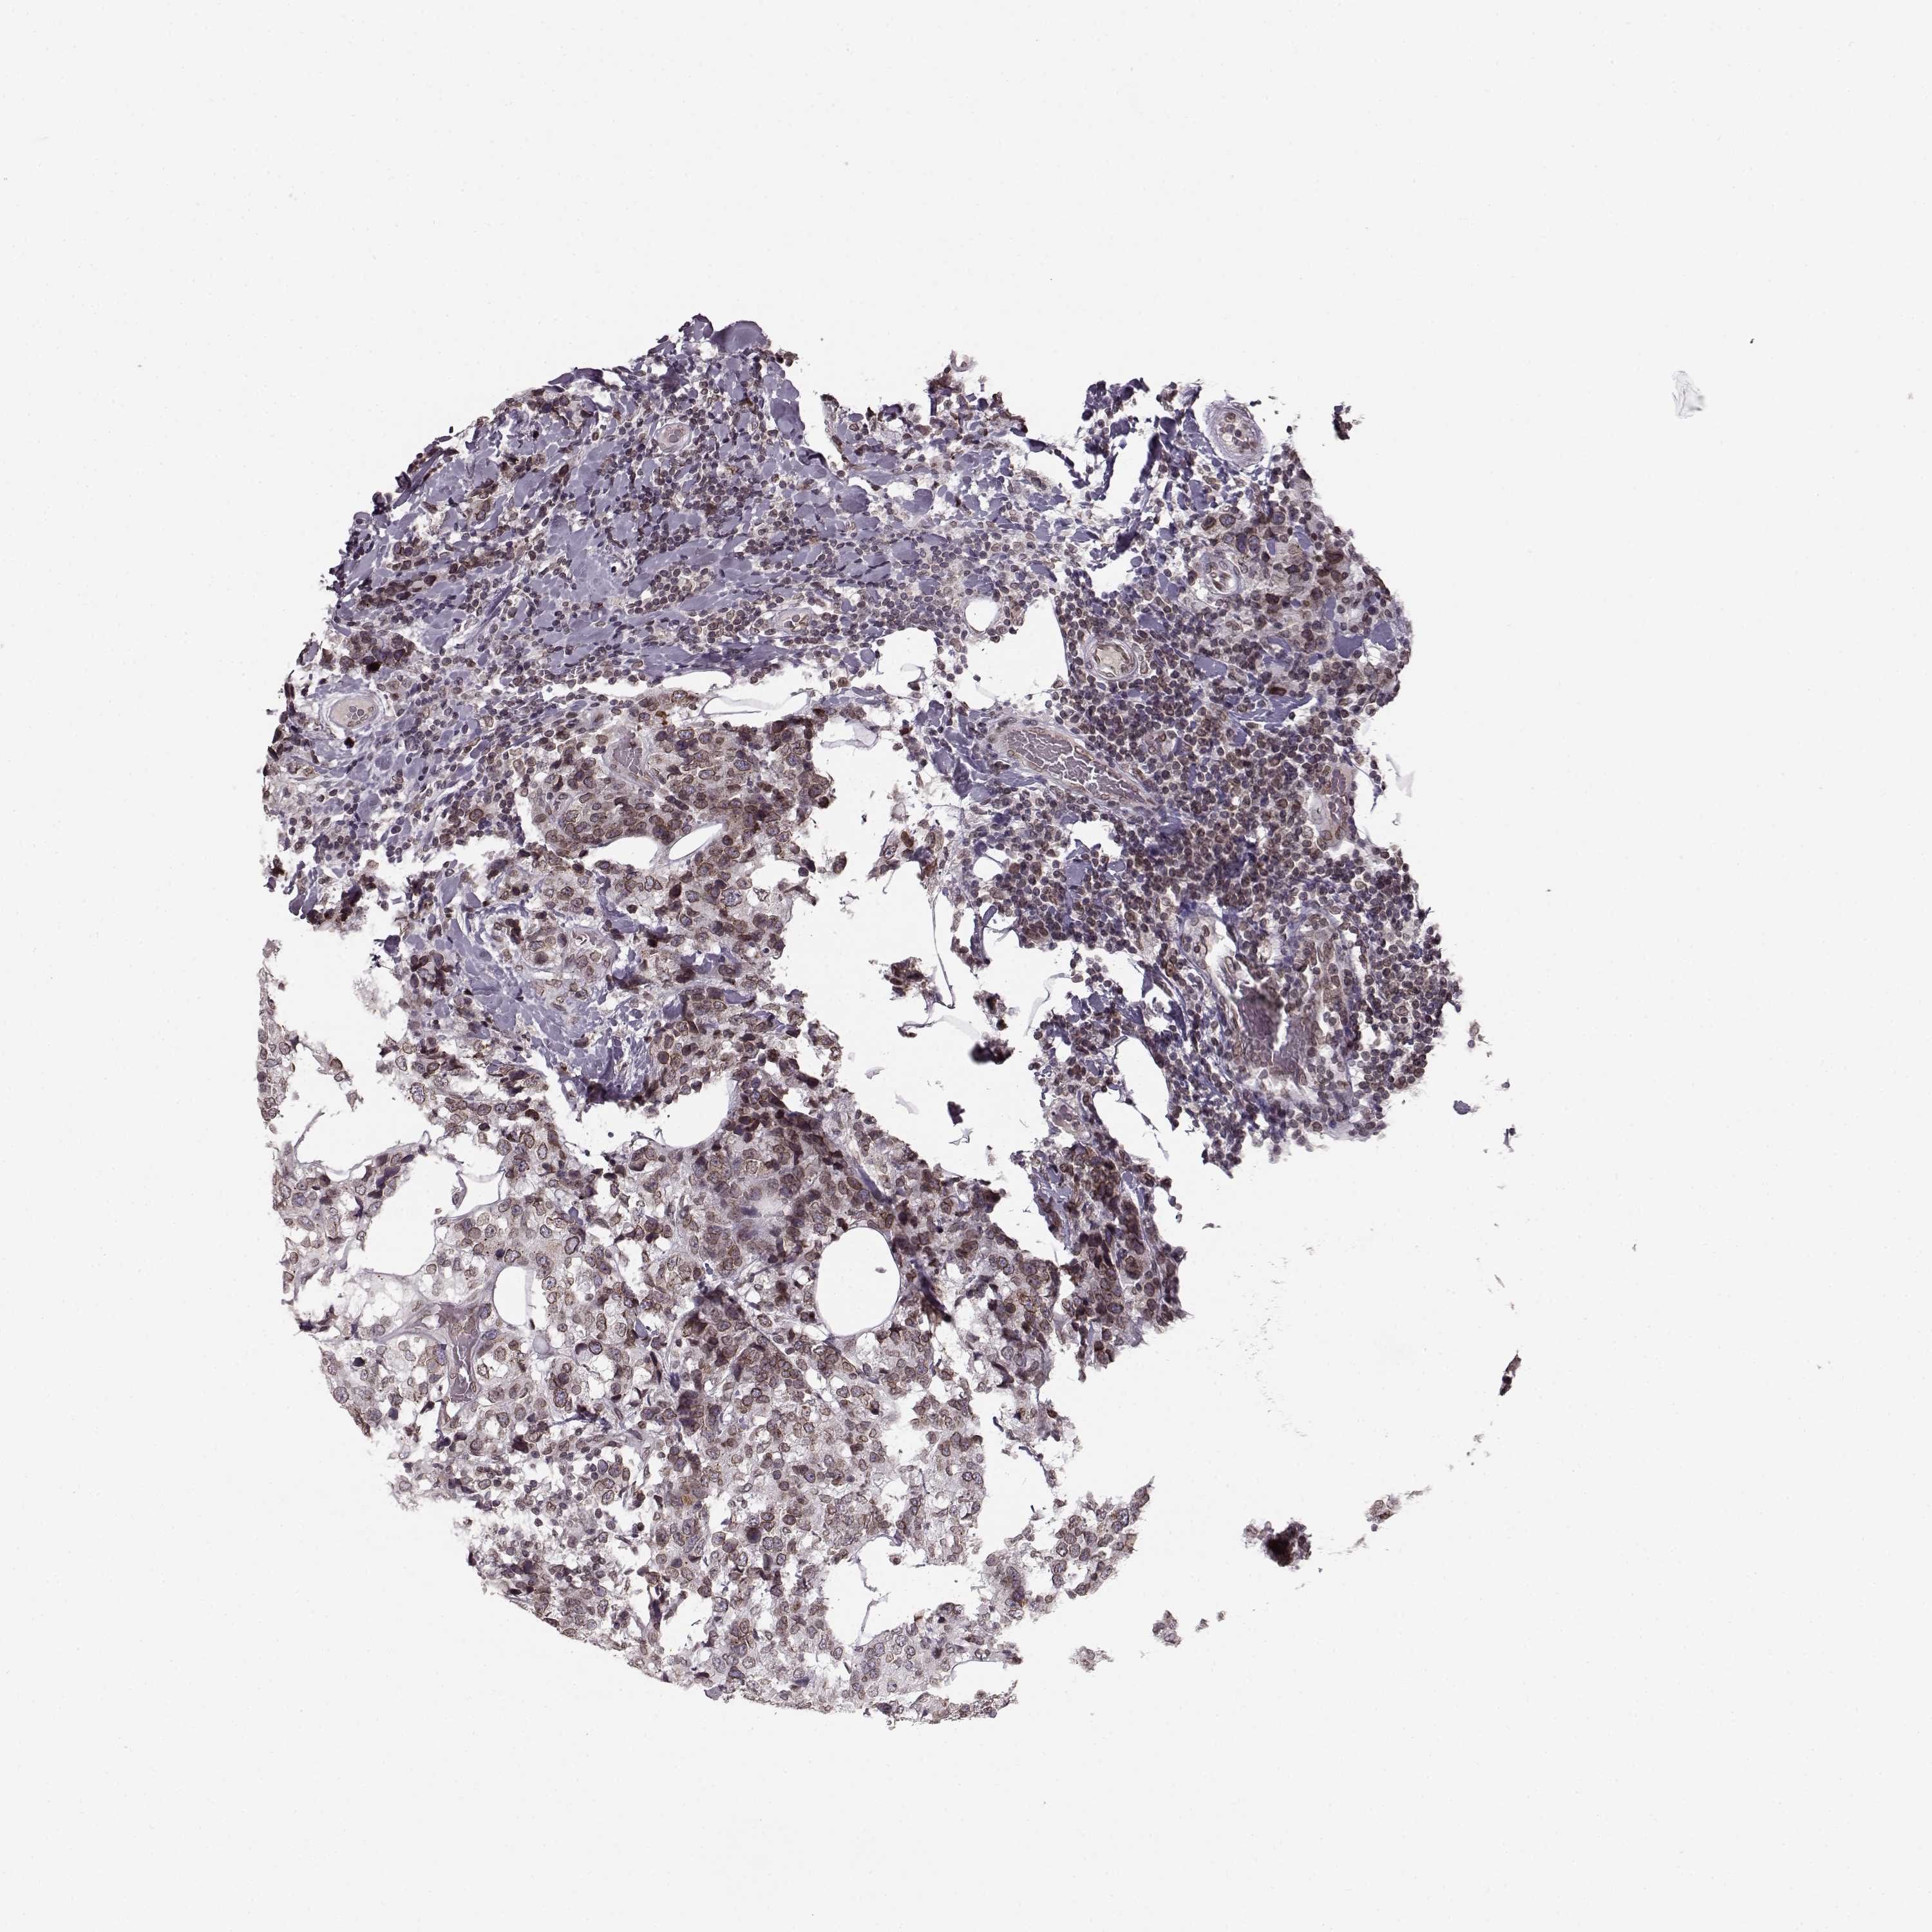

BRCA TCGA BRCA VALIDATION PROTEIN EXPRESSION